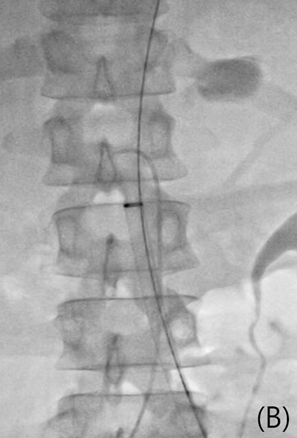

Cobra catheter로 교체하여 상위장간막동맥 조영술을 시행하였을 때 상위장간막동맥의 혈류는 원활하였음. 카테터를 상위장간막동맥 입구에 거치한 상태로 왼쪽 온넙다리동맥을 천자하여 6Fr sheath를 거치하고 guidewire를 이용하여 진입시킬 때 대동맥 손상 부분을 통해 guidewire가 나가는 것이 확인됨 (Fig. 3A). 이 때 guidewire 부분이 반드시 스텐트-그래프트로 덮어야 할 부분이고, 카테터가 있는 부분이 반드시 스텐트-그래프트로 덮지 말아야 할 부분이라 할 수 있음. 이후 왼쪽 온넙다리동맥 천자부위를 Preclose technique으로 16Fr sheath로 교체하고 (Fig. 3B) Gore excluder aortic extender 23 mm x 3.3 cm를 성공적으로 설치하였음(Fig. 3C).

Fig 3A

(A) A 0.035-inch guidewire and a 5 Fr Cobra catheter were located in lumen of ruptured pseudoaneurysm (must be covered) and os of superior mesenteric artery (should never be covered), respectively.

Fig 3B

(B,C) Aortic stent-graft (GORE EXCLUDER 23mm/3.3cm) was deployed to cover ruptured pseudoaneurysm with left common femoral approach using 16 Fr sheath and preclose manner.

Fig 3C